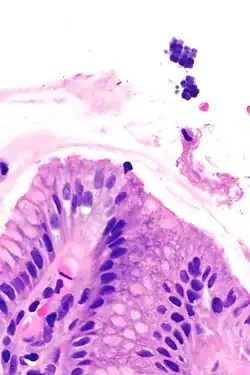

| Gastric mucosa and Sarcina on upper right. H&E stain. | |